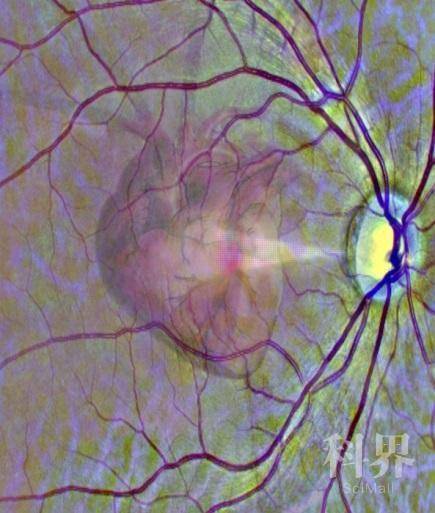

通过视网膜扫描来了解心脏健康状况(示意图)。

图片来源:利兹大学官网